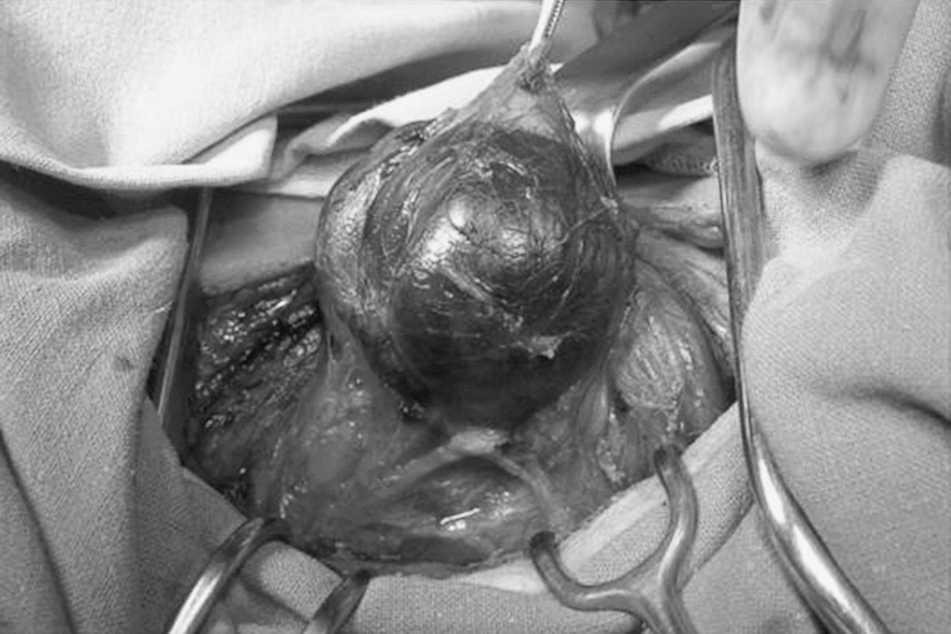

Paciente varón de 47 años, sin antecedentes de interés, consulta por tumoración no dolorosa laterocervical derecha. No presenta síntomas deglutorios ni alteraciones en la voz. La exploración revelaba una tumoración en la región cervical anterior izquierda, elástica, de unos 6 cm de diámetro. La ecografía informó de imagen quística dependiente del polo inferior tiroideo de 55 x 44 x 37. La gammagrafía tiroidea resultó normal. La analítica mostró unos valores normales de hormonas tiroideas, la paratirina (PTH) fue de 90 pg/ml (normal, 9-60 pg/ml), la calcemia de 11,2 mg/dl (normal, 8,1-10,4 mg/dl) y fosforemia de 4,3 mg/dl (normal, 2,7-4,5 mg/dl). Se realizó una punción-aspiración con aguja fina (PAAF) del quiste, y se obtuvo 6 ml de líquido transparente, cuya determinación de PTHi fue de 3.450 pg/ml. Se estableció el diagnóstico de quiste paratiroideo. Por la situación de hiperparatiroidismo se indicó la intervención del paciente y se extirpó un quiste dependiente de la glándula paratiroides inferior (fig. 1), la superior era normal. La determinación intraoperatoria de PTHi se refleja en la figura 2, corrigiéndose la situación de hiperparatiroidismo. El paciente se encuentra asintomático pasados 28 meses.

Fig. 1. Quiste paratiroideo. Campo operatorio.